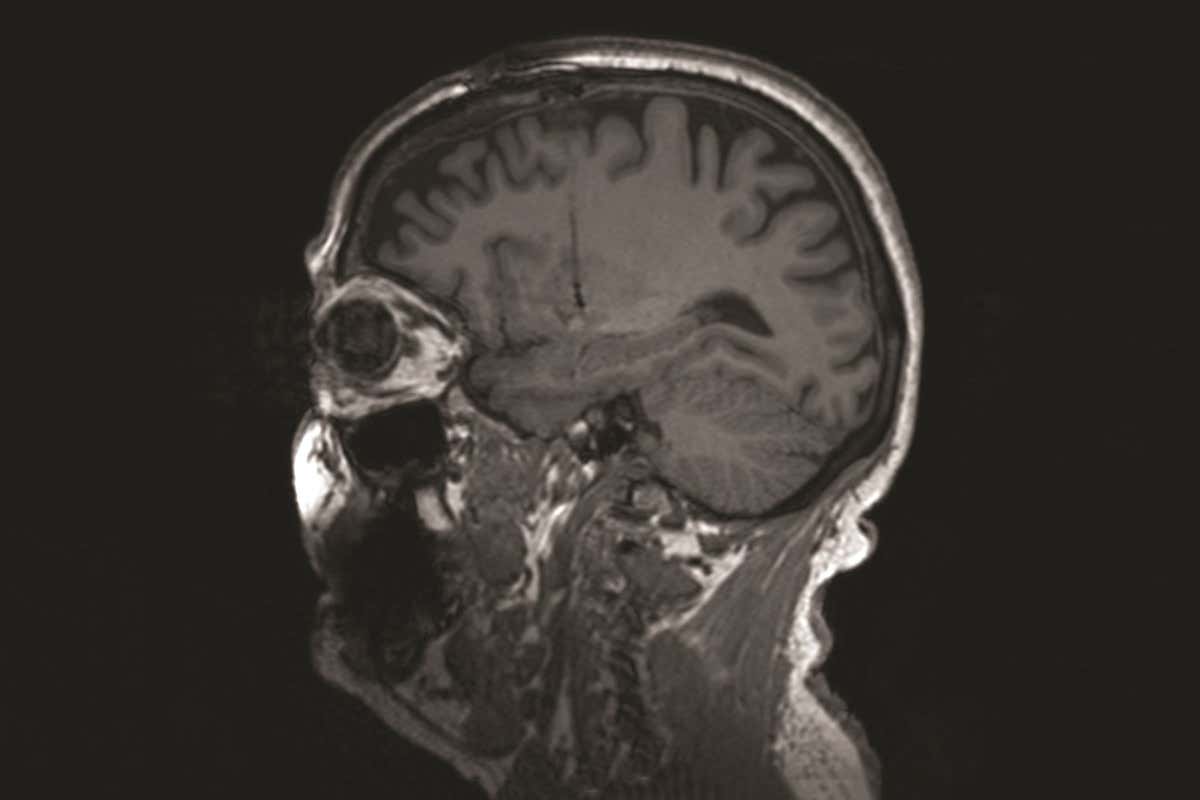

The disease is caused by the gradual loss of dopamine-producing cells GJLP/Science Photo Library

The disease is caused by the gradual loss of brain cells that make dopamine, a compound that helps control our movements. Current medicines replace the missing dopamine, but their effectiveness wears off over the years.